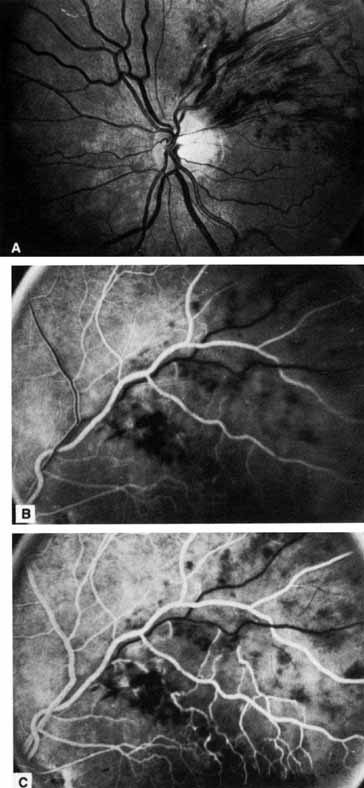

Fig. 1 A. “Blood and thunder” appearance of a central retinal vein occlusion. B. Intravenous fluorescein angiogram shows this occlusion is primarily ischemic or nonperfused. The fact that there is more nonperfusion in the inferior half of the fundus compared with the superior half is unusual.

Coats55 may have been the first to suggest that patients with central retinal vein occlusion fall into two groups: one with a dramatic, “blood and thunder” ophthalmoscopic appearance, loss of vision, and a poor prognosis (see Fig. 1); and the other with mild ophthalmoscopic changes, generally good visual acuity, and a relatively good prognosis (Fig. 2). Other investigators have commented on the difference in severity among central retinal vein occlusions, relying principally on the fluorescein angiogram to assess the severity of occlusion.56–59

Fig. 2 A. Nonischemic central retinal vein occlusion. Note venous engorgement, dot, blot, and flame-shaped hemorrhages, blurring of disc margins, and a hemorrhage overlying the macula. B. Fluorescein angiogram reveals mild venous engorgement and tortuosity with virtually no capillary nonperfusion.

The ophthalmoscopic features of nonischemic central retinal vein occlusion are similar to those of ischemic central retinal vein occlusion, but are much less extensive (see Fig. 2; Fig. 3A and 3B). Engorgement of the venous tree (including the capillaries) is prominent; there is increased tortuosity and dilation and a darker appearance of the blood column. Retinal hemorrhages vary markedly. Sometimes they occur only peripherally; at other times, they may be rather prominent in the posterior pole.60 Cotton-wool spots are rare. Vision may be decreased because of macular edema or macular hemorrhage.

Fig. 3 A and B. Acute nonischemic central retinal vein occlusion in a 36-year-old hypertensive man. His visual acuity was 20/200. C and D. Six weeks later, he presented with eye pain, decreased vision, and neovascular glaucoma. The type of occlusion now is ischemic.

The intravenous fluorescein angiogram pattern of an ischemic central retinal vein occlusion is usually characterized by a delayed filling time of the venous tree of the retina, capillary and venous dilation, and extensive leaking of fluorescein into the retina, particularly in the macular area and in the area adjacent to the larger venous trunks and capillary nonperfusion (see Fig. 3C and 3D; Figs. 4 and 5). Microaneurysms may not be noted at the time of initial occlusion, but are usually manifest shortly thereafter. Late-phase photographs show patchy extravascular areas of fluorescence and staining of the retinal veins. Fluorescence in the macula indicates capillary leakage and edema; this not only may account for much of the initial visual loss in the acute phase, but may also eventually result in permanent structural changes. Intravenous indocyanine green videoangiography may also be helpful in showing the arterial and venous flow alterations in this condition.322

Fig. 4 Fluorescein angiogram after moderately ischemic central retinal vein occlusion. A. Early venous phase. The capillary bed is dilated and engorged. Punctate areas of fluorescence represent microaneurysms or small areas of capillary leakage. B. Midvenous phase. There is considerable delay in venous return and an increase in and coalescence of punctate areas of extravascular fluorescence. C. Late venous phase. Fluorescence staining along the vein margins and scattered areas of capillary nonperfusion (arrow) are present.

Fig. 5 Fluorescein angiogram of acute ischemic retinal vein occlusion. Capillary nonperfusion is essentially 100%.